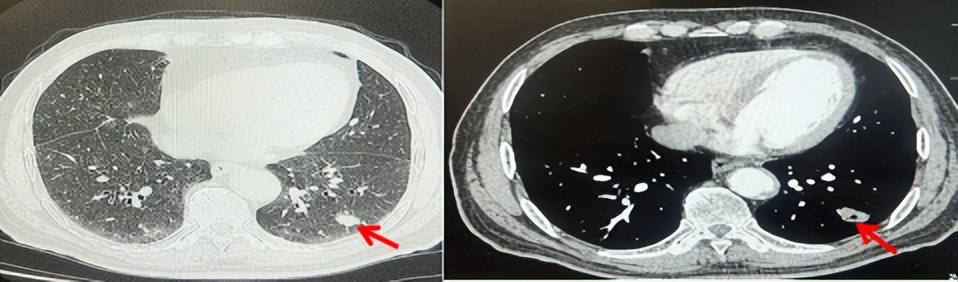

69岁男性,无糖尿病、高血压、心脏病等基础疾病,无吸烟、饮酒史,无肿瘤家族史。2023.06.07行胸部CT检查:右肺上叶胸膜下见肿物影,大小约33mm×22mm,边缘可见分叶,考虑恶性病变可能性大,双肺间质改变(如图1)。2023.06.14行“单孔胸腔镜下右肺上叶切除、肺门及纵隔淋巴结清扫、胸膜粘连松解术”;术后病理:(右肺上叶)腺癌(低分化,实体型占60%,不良腺体占40%),局灶伴神经内分泌标记表达(CD56、Syn),可见STAS及胸膜侵犯,未见确切神经侵犯及脉管内癌栓;(气管切缘)净;(淋巴结)未见转移癌0/26(2组0/2;4组0/6;7组0/2;对侧7组0/8;10组0/2;11组0/3;12组0/2;13组0/1)。术后分期pT2aN0M0 IB期,术后NGS基因检测:无驱动基因突变,PD-L1(22C3)TPS<1%。术后定期复查。

2024.11.19患者出现右侧胸痛,复查胸部CT检查示右侧胸膜肿物,大小约31mmX24mm,右侧4、5肋骨骨质破坏,考虑转移(如图2)。建议患者穿刺活检取病理明确诊断,患者拒绝,经MDT会诊后结合影像学表现及病史考虑为胸膜转移,肋骨转移,分期为rT0N0M1a IVA期,DFS仅仅17个月。2024.12.05起行信迪利单抗联合培美曲塞+卡铂方案治疗4周期,复查胸CT评效PR(如图3)。之后给予信迪利单抗+培美曲塞维持治疗6周期,期间复查CT评效PR(如图3)。目前信迪利单抗+培美曲塞维持治疗中,截止至目前PFS约为8个月,治疗期间未出现明显毒副反应。

图1:患者手术前(2023.06)胸部CT肺窗及纵隔窗

图2:患者胸膜及肋骨转移(2024.11)胸部CT肺窗、纵隔窗及骨窗

图3:患者免疫联合化疗治疗后胸部CT,(A、B)图展示信迪利单抗联合培美曲塞+卡铂治疗

4周期(2025.02)疗效,(C、D)图展示信迪利单抗+培美曲塞维持治疗6周期(2025.07)疗效